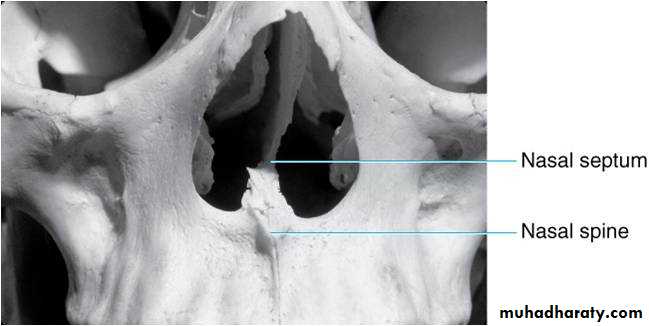

Drawing of maxillary midline area. Shown are the (1) outline of nose, (2) incisive foramen , (3) lateral fossa, (4) nasal fossa, (5) nasal septum, (6) border of nasal fossa, (7) anterior nasal spine, and (8) median palatine suture

Radiographic Anatomy Basics